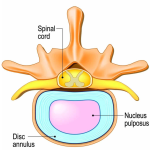

Understanding De Quervain’s Tenosynovitis: What’s Causing That Pain in Your Wrist?  Understanding Disc Bulge: A Vital Guide From Movement Science Physiotherapy

Understanding Disc Bulge: A Vital Guide From Movement Science Physiotherapy Understanding Frozen Shoulder: What It Is and How to Treat It